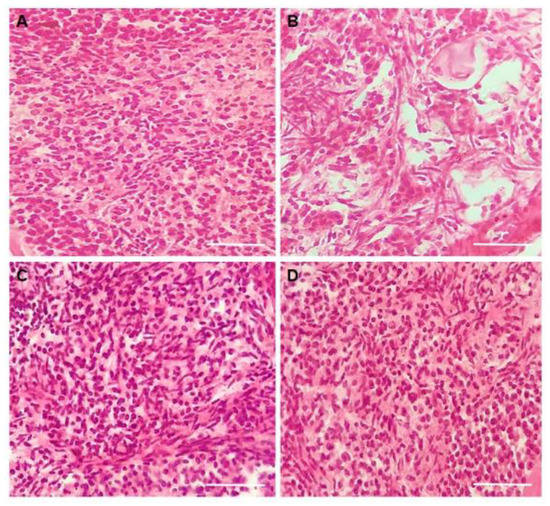

3.3. Experiment 2: Potential of CIMI to Reduce Damage Caused by DOXO on In Vitro Culture of Mouse Ovaries

3.4. Immunohistochemical Localization of Active Caspase-3 in Mice Cultured Ovary

3.6. Evaluation of Stromal Cells Density after In Vitro Culture of Mice Ovaries